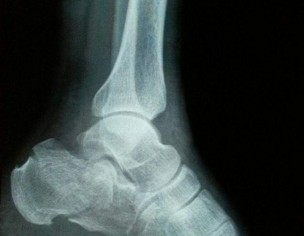

My father fell off from height 3 weeks back and got his left calcaneus fractured. We saw a doctor the same day who applied plaster cast on his foot and adviced icing and foot elevation Later, we saw another doctor who adviced cast removal immediately and starting physiotherapy and exercises. The latter also said that cast should not have been applied in this particular case. Also, the cast application on the same day of fracture could cause ischemia due to impending swelling.

this fracture need surgery for better functional outcome

This needs surgery